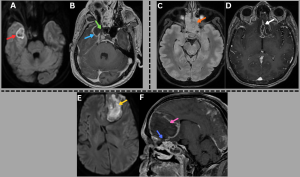

Fig 14: Case 1 -

Clinical history:

A 45-year-old patient with poorly controlled diabetes mellitus presented with fever, cough, and pleuritic chest pain.

Figure A:

Erect AP chest radiograph demonstrates multiple inhomogeneous air-space opacities in the bilateral lung fields (green arrows).

Figures B and C:

Coronal and axial HRCT images demonstrate multiple lesions with central ground-glass attenuation surrounded by a peripheral rim of consolidation in both lungs (red arrows), consistent with the reverse halo sign.

.......Case 2 -

A 50-year-old immunocompromised male presented with acute febrile illness and hemoptysis.

Figures D and E:

Axial and coronal HRCT images demonstrate multifocal areas of consolidation with surrounding peripheral ground-glass attenuation (orange arrows), representing the halo sign. Additional ill-defined ground-glass opacities are noted in the bilateral lung fields (blue arrows).

Vascular involvement leads to pulmonary infarction, and parenchymal necrosis is common, resulting in consolidation or mass-like lesions with a centrally hypodense, nonenhancing component and a relative paucity of air bronchograms, termed the "hypodense nodule sign". This finding may precede cavitation, although cavitation can occasionally be the initial imaging manifestation.

Fig 15: Clinical history:

A 42-year-old patient with diabetic ketoacidosis presented with persistent fever and dry cough.

Axial HRCT chest image demonstrates a focal area of consolidation in the superior basal segment of the right lower lobe (orange arrow).

Axial non-contrast and post-contrast CT chest images demonstrate a central low-attenuation, nonenhancing focus within the consolidation (green arrows), consistent with the hypodense nodule sign.

Axial and sagittal post-contrast CT chest images demonstrate abrupt cut-off and nonvisualization of an adjacent segmental/subsegmental pulmonary arterial branch (red arrows), consistent with the vascular cut-off sign, reflecting underlying vascular involvement in invasive pulmonary mucormycosis.

Fig 18: Clinical history:

A 36-year-old immunocompromised female with a history of renal transplantation on long-term immunosuppressive therapy presents with fever, cough, and hemoptysis.

High-resolution CT (HRCT) chest image demonstrates consolidation in the right middle and lower lobes (red arrow) with associated centrilobular ground-glass nodules.

Figures B & C:

Axial and coronal contrast-enhanced CT (CECT) chest images demonstrate aneurysmal dilatation of the right interlobar pulmonary artery (green arrow) with an associated intimal flap (orange arrow), consistent with a dissecting pulmonary artery aneurysm.

Figure D:

Histopathology demonstrates necrotic lung parenchyma with alveolar spaces (blue arrow). The magnified view reveals broad, pauciseptate fungal hyphae (black arrow), confirming mucormycosis.